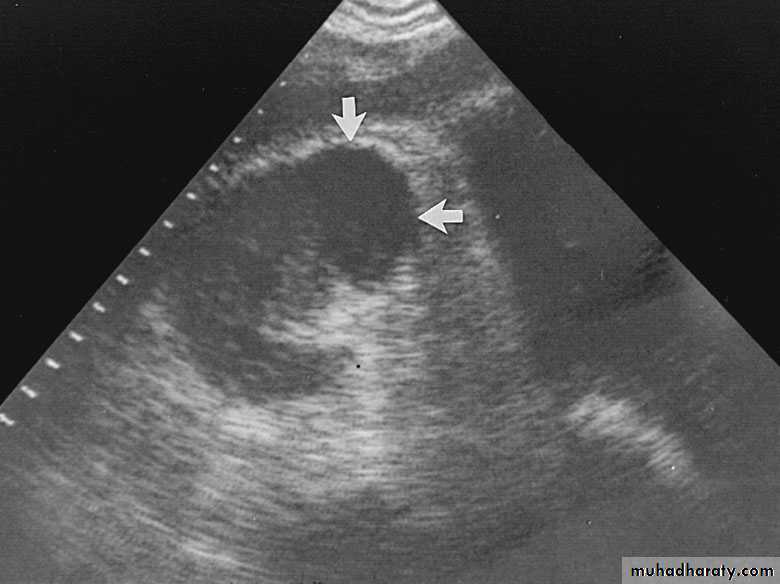

Renal Abscess or Renal Carbuncle

Renal abscess or carbuncle is a collection of purulent material confined to the renal parenchyma.The renal parenchyma contains an encapsulated necrotic mass

Insidious onset (may run > 2 weeks)

Obscure fever

Local pain

Symptoms of the primary cause

Tender renal angle

Tender mass : differentiate from malignant lesion

Investigations

U/S

KUB, IVU

CT scan

Treatment

Medical: RestAnalgesia

Antibiotics

Follow up examination

Surgical: Abscess drainage

Nephrectomy

Perinephric Abscess

Route of infection:Rupture of renal abscess

Infected perinephric hematoma or urinoma

Cortical abscess coallese, enlarge, rupture to the perinephric space, form a perinephric abscessFluid filled inflammatory mass